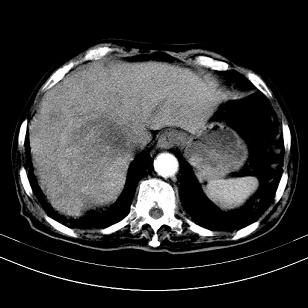

标题: CT19407:肝内还是肝外原发性肿瘤??

男,63岁,高血压病史40余年,

考虑右肝后叶肝癌伴多发肝内转移

考虑右肝后叶肝癌(部分外生)伴肝内多发性转移;右侧肾上腺区恶性肿瘤并肝转移待排。

考虑右肝后叶肝癌(部分外生)伴肝内多发性转移

支持肝癌肝内转移,肝硬化。

支持肝右叶巨块型肝癌伴肝内转移.

考虑右肝后叶肝癌(外生型)伴肝内转移。

肝右叶外生性肝癌,伴肝内转移

支持肝右叶巨块型肝癌伴肝内转移。